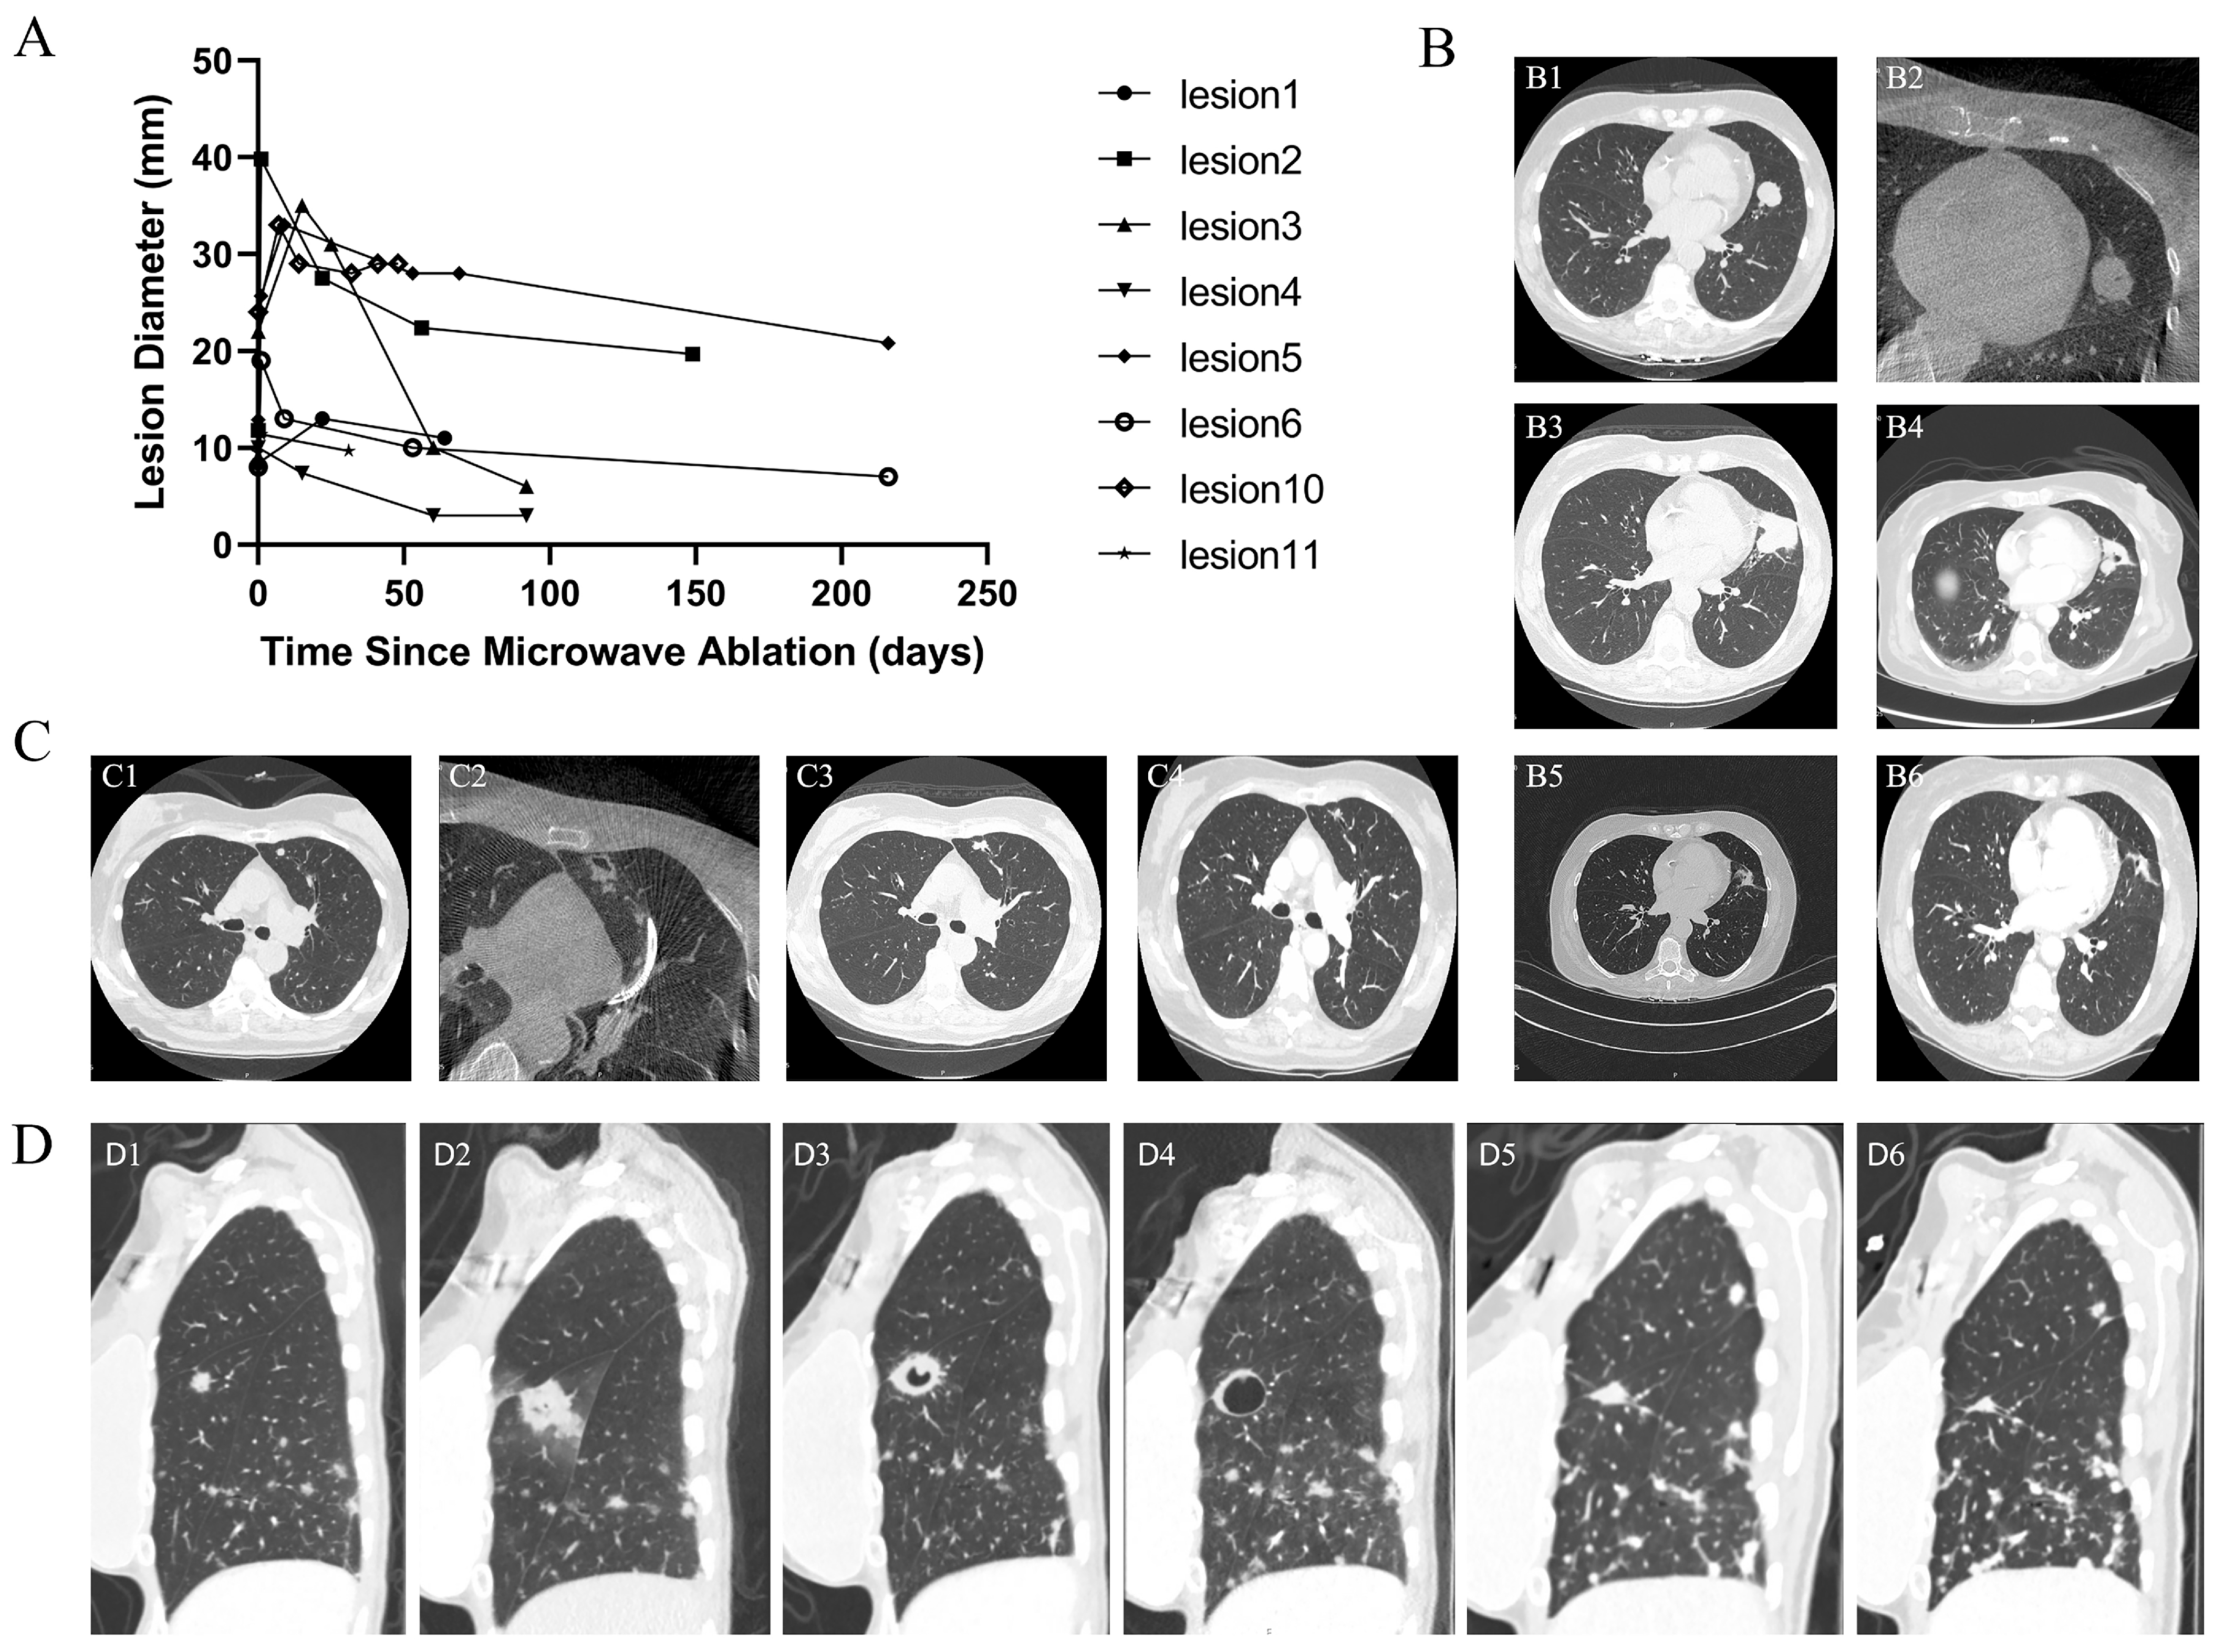

3.4. Imaging Evolution After Ablation

3.5. Efficacy of Microwave Ablation for Primary Lung Cancer

3.6. Early Efficacy of Microwave Ablation for Metastatic Lung Lesions